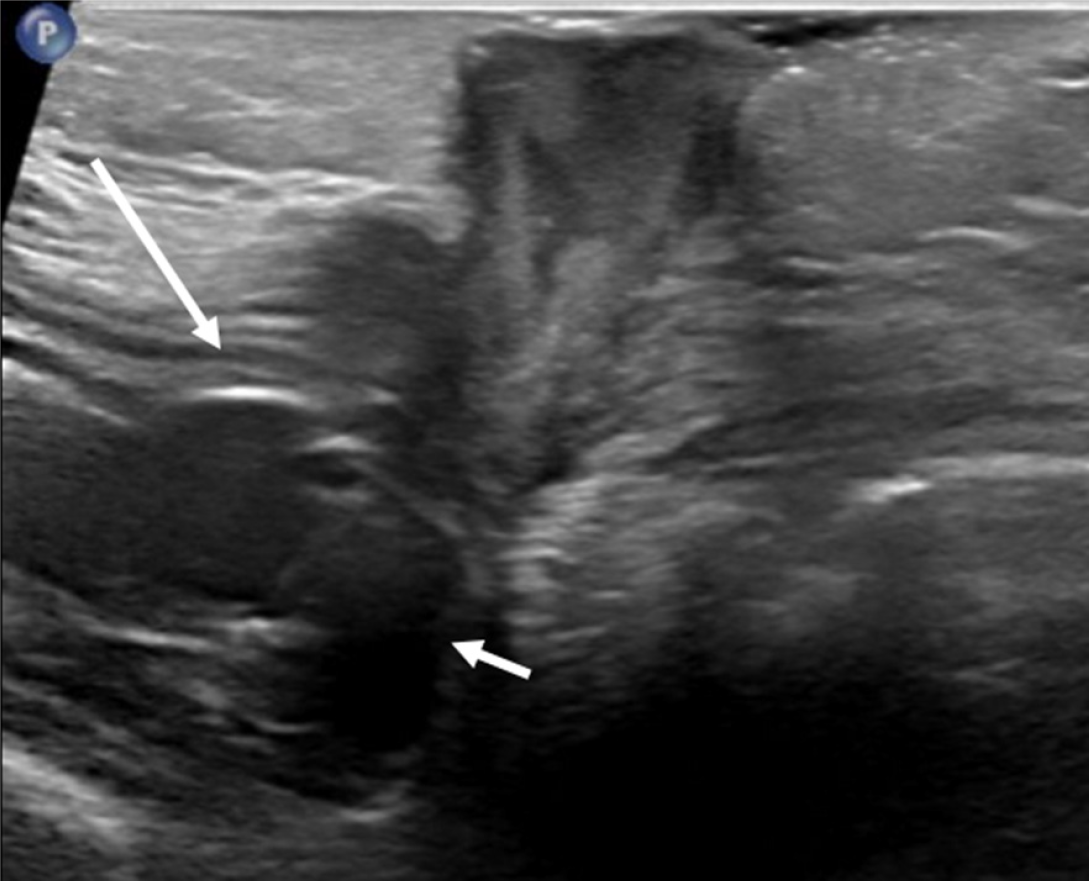

Figure 14 Local abscess.

A 9 year old with gastrostomy tube (G-tube) site swelling. Ultrasound shows a complex fluid collection/abscess in the subcutaneous soft tissues. The gastric wall (long arrow) and G-tube balloon (short arrow) are well seen without evidence of intraperitoneal fluid or air.